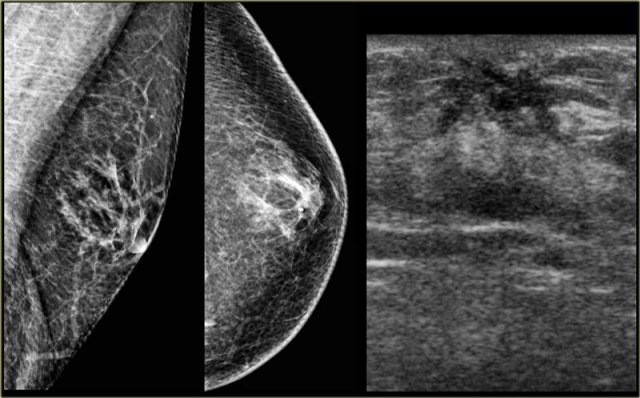

Mammogran and rotated ultrasound image Mammogran and rotated ultrasound image

Nodular pattern

The nodular pattern of gynecomastia is seen in the florid early phase.

It begins as an increased number of ducts and epithelial proliferation with edema and cellular fibroblastic stroma.

This phase is reversible.

On the left a mammogram and an ultrasound image of a patient with a nodular glandular pattern of gynecomastia.

Notice that it is situated underneath the nipple.

The ultrasound image shows the typical appearance of gynecomastia: a hypoechoic mass with lobulation or even spiculation.

If this was seen in a woman, you would say that this is a mass with microlobulation and spiculation, i.e. Birads IV or V.

In a man this is typical for gynecomastia.

On the left the same ultrasound image, but now in the normal position.

Notice how 'malignant' it looks.